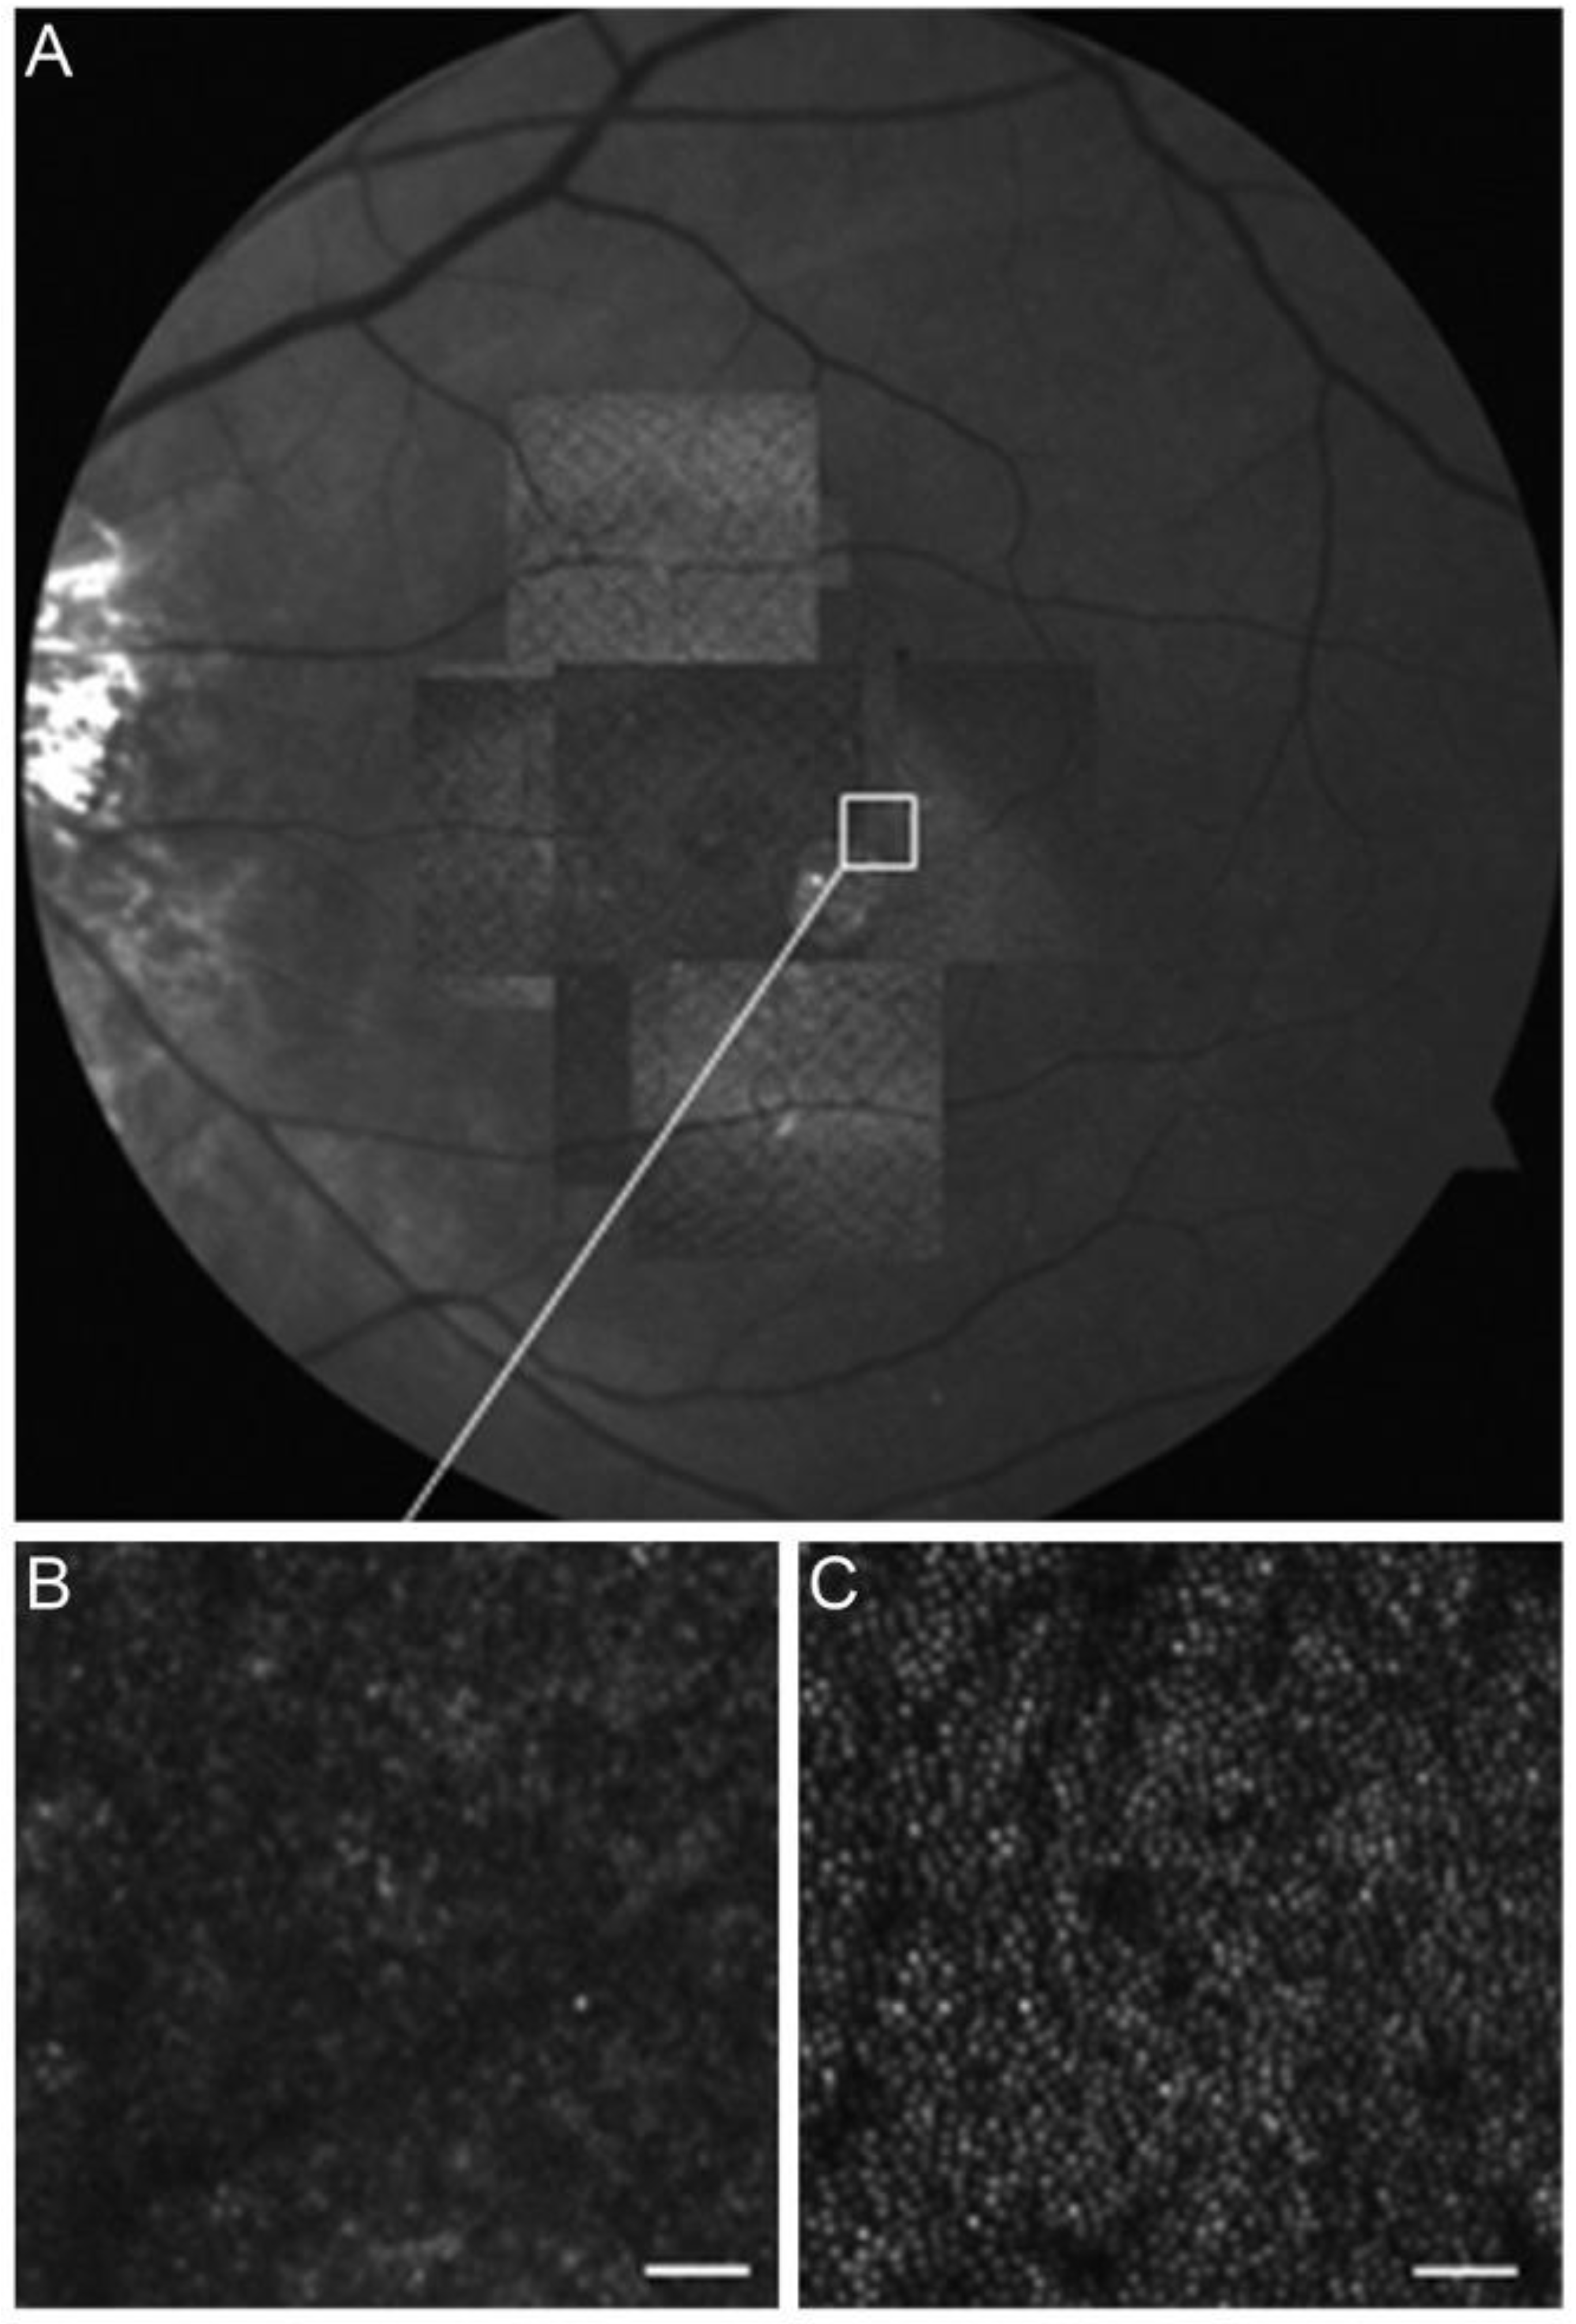

3.5. Adaptive Optics

- Debellemanière, G.; Flores, M.; Tumahai, P.; Meillat, M.; Bidaut Garnier, M.; Delbosc, B.; Saleh, M. Assessment of Parafoveal Cone Density in Patients Taking Hydroxychloroquine in the Absence of Clinically Documented Retinal Toxicity. Acta Ophthalmol. 2015, 93, e534–e540. [Google Scholar] [CrossRef] [PubMed]

- Babeau, F.; Busetto, T.; Hamel, C.; Villain, M.; Daien, V. Adaptive Optics: A Tool for Screening Hydroxychloroquine-Induced Maculopathy? Acta Ophthalmol. 2017, 95, e424–e425. [Google Scholar] [CrossRef] [PubMed]

- Ueda-Consolvo, T.; Oiwake, T.; Abe, S.; Nakamura, T.; Numata, A.; Hayashi, A. Hydroxychloroquine’s Early Impact on Cone Density. J. Ophthalmol. 2021, 2021, 1389805. [Google Scholar] [CrossRef] [PubMed]

- Stepien, K.E.; Han, D.P.; Schell, J.; Godara, P.; Rha, J.; Carroll, J. Spectral-Domain Optical Coherence Tomography and Adaptive Optics May Detect Hydroxychloroquine Retinal Toxicity before Symptomatic Vision Loss. Trans. Am. Ophthalmol. Soc. 2009, 107, 28–33. [Google Scholar]